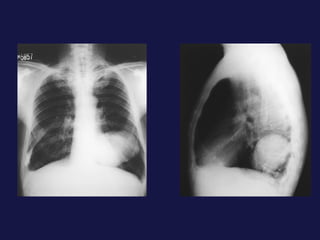

Tumor central. 60-75% próximos a los hilios. Epidermoides y células pequeñas. Agrandamiento asimétrico del hilio o masa de bordes espiculados. Atelectasia lobular, segmentaria o de todo el pulmón. Sobreinfección del parénquima distal y neumonía postobstructiva, a menudo abscesificada.

Tumor central. 60-75%próximos a los hilios. Epidermoides y células pequeñas. Agrandamiento asimétrico del hilio o masa de bordes espiculados. Atelectasia lobular, segmentaria o de todo el pulmón. Sobreinfección del parénquima distal y neumonía postobstructiva, a menudo abscesificada.